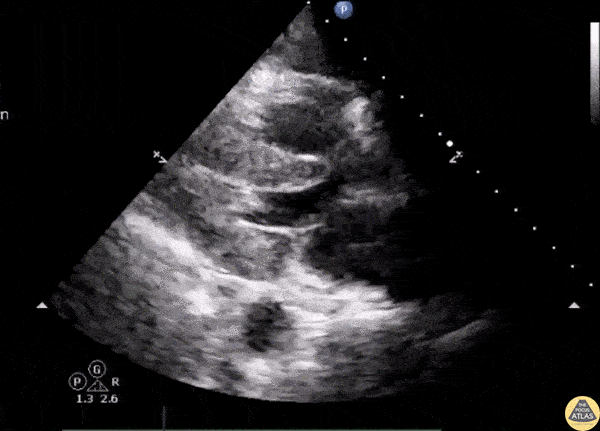

Valvulopathy - Left Ventricular Outflow Tract Obstruction

Septic patient with hypotension shows LVOT obstruction with systolic anterior motion of the mitral valve on echo. Image courtesy of Robert Jones DO, FACEP @RJonesSonoEM Director, Emergency Ultrasound; MetroHealth Medical Center; Professor, Case Western Reserve Medical School, Cleveland, OH View his original post here